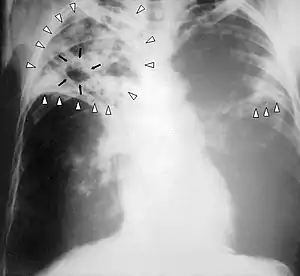

![]() Рентгенограма органів грудної клітки пацієнта з прогресуючим туберкульозом. Білі стрілки вказують на вогнища хвороби в обох легенях. Чорні стрілки вказують на сформовану порожнину (каверну). Рентгенограма органів грудної клітки пацієнта з прогресуючим туберкульозом. Білі стрілки вказують на вогнища хвороби в обох легенях. Чорні стрілки вказують на сформовану порожнину (каверну). | |